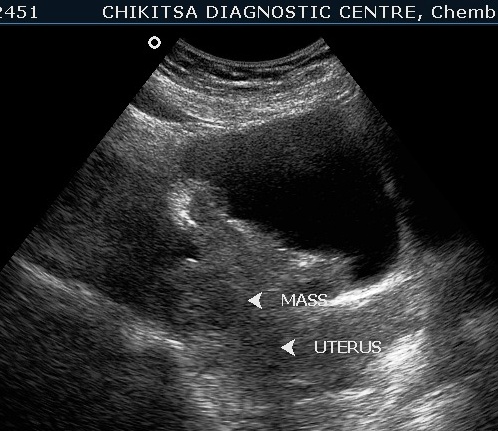

July-Aug 2012 :

Left kidney shows hydronephrosis.

Lesion in the wall of the urinary bladder has increased in size. Calcific areas are noted. Urinary bladder malignancy ( confirmed by histopathology), possibly following schistosomiasis.